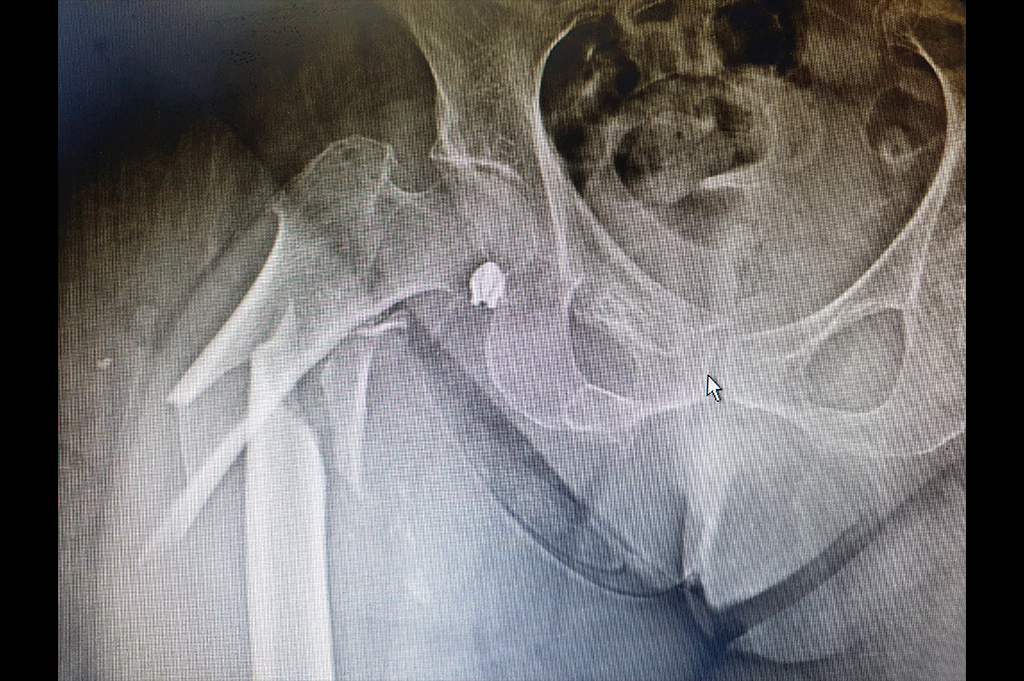

Total Hip Replacement - THR